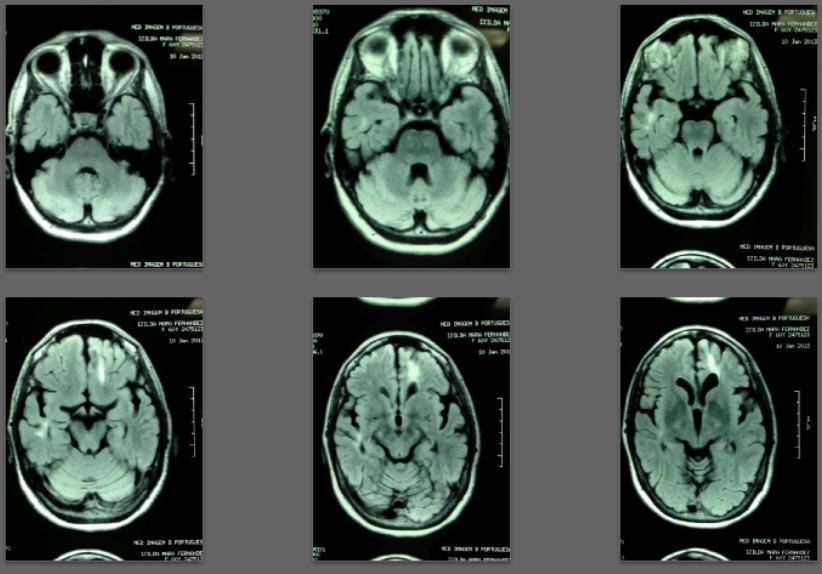

Before/after MRI images for one of 1,000+ patients of Dr. Coimbra

2008 Convulsive seizures Diagnosis: Balo’s concentric hemiparesis

Starting daily dose 25,000 IU; increased in stages to 80,000 IU on October 28, 2010. Asymptomatic since 2010.

2013 MRI